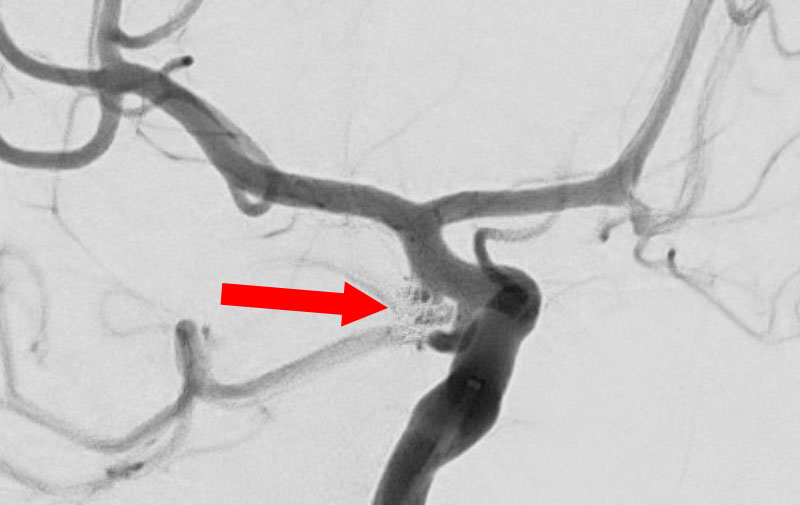

No.1631 手術後